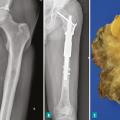

Prise en charge chirurgicale des sarcomes osseux

La résection d’un sarcome osseux a pour objectif d’obtenir des marges adaptées, en privilégiant les chirurgies conservatrices, tout en s’efforçant de préserver la meilleure qualité de vie.1 La chirurgie doit être effectuée par une équipe spécialisée dans un centre de référence intégré au réseau NetSarc+, ce qui diminue le risque de…